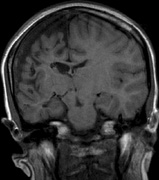

Optic nerve gliomas may involve the optic chiasm and be associated with endocrine disorders or nystagmus.68–70 Surgical excision of chiasmal gliomas (Fig. 6) carries a high risk of visual loss. Invasion of the hypothalamus or the third ventricle carries a poor prognosis, with greater than 50% 15-year mortality rate.71 One review of radiation treatment for chiasmal gliomas collated data from small case series and found no significant long-term improvement in visual function, progression, or mortality with radiation treatment.71 Other reports suggest that radiation doses over 4500cGy improve symptoms and slow progression of chiasmal gliomas over several years.72 Adequate tumor coverage by radiotherapy results in irradiation of normal brain and nearly all children need hormone replacement.73 Chemotherapy is an alternative.74,75

Fig. 6. Surveillance images of a 12-year-old girl with NF1 and an optic nerve glioma which has extended to involve the chiasm. Pre- (a) and postcontrast (b) T1-weighted coronal images reveal a large suprasellar mass with an enhancing component (arrow) seen separately from the normally enhancing pituitary gland. (c) Axial scans through the suprasellar cistern show the tumor is high signal on T2-weighted scans. (d) Enlargement of the chiasm, optic nerve and hypothalamus is visible on the post-contrast T1-weighted sagittal image. Although optic nerve glioma usually has a good prognosis (with visual function often remaining stable in the absence of any intervention66,67), chiasmal involvment is a poor prognostic indicator. A sign of chiasmal involvment may be new onset of endocrine disorders or nystagmus. Surgical excision of chiasmal gliomas carries a high risk of visual loss.68–70